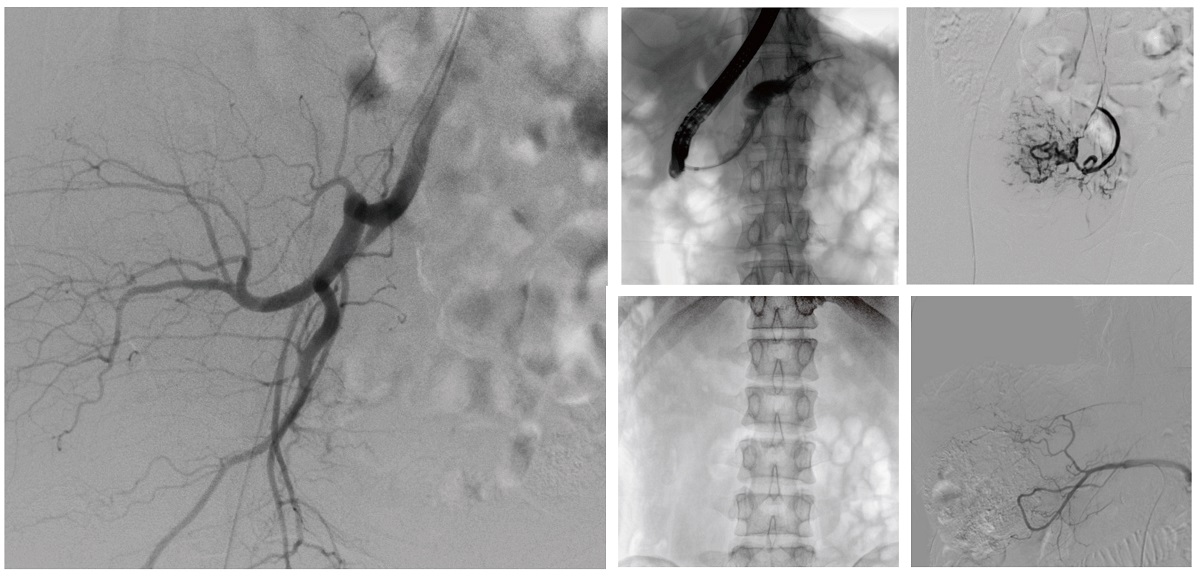

醫院引進的普愛醫療移動式平板介入中C,其高清成像能力覆蓋骨科、介入科、泌尿外科、婦產科等多科室,能夠滿足介入微創手術的多樣化需求。

設備的移動式設計,無需對現有手術室進行改造,適合高負荷手術量或應急情況下的靈活部署。如在急診介入手術中,該設備能迅速響應需求,為醫生提供實時影像支持,提升搶救效率。